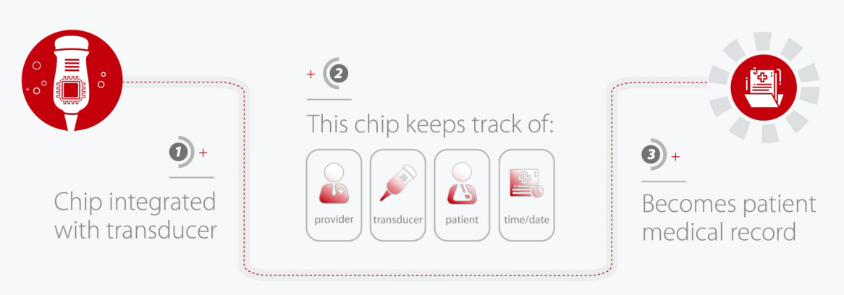

Chip-embedded transducers (Z-Tracking), can assist in identify the source of infection and can provide quarantine control evidence.